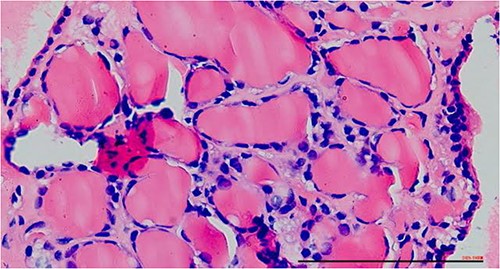

The right mass (Fig. 5) was even bigger and needed an extension of incision into the neck (Fig. 6). About 7 cm × 7 cm noted to be displacing Superior venacava anteriorly that was dissected from it, separated from the first rib and subclavian artery meticulously taking care not to damage any major structure. Both masses were excised. These masses were not connected in any way with each other as well as with the orthotopic thyroid in the neck. Post-op was uneventful. Thyroid functions were normal. Thyroid scan (Fig. 8) showed no evidence of a thyroid tissue in the mediastinum and no other ectopic thyroid was present other than the orthotopic thyroid tissue in neck. The patient was discharged on POD 10 without any symptoms. The histopathological tissue diagnosis showed a colloid goiter (Fig. 7). All data kept in our database.